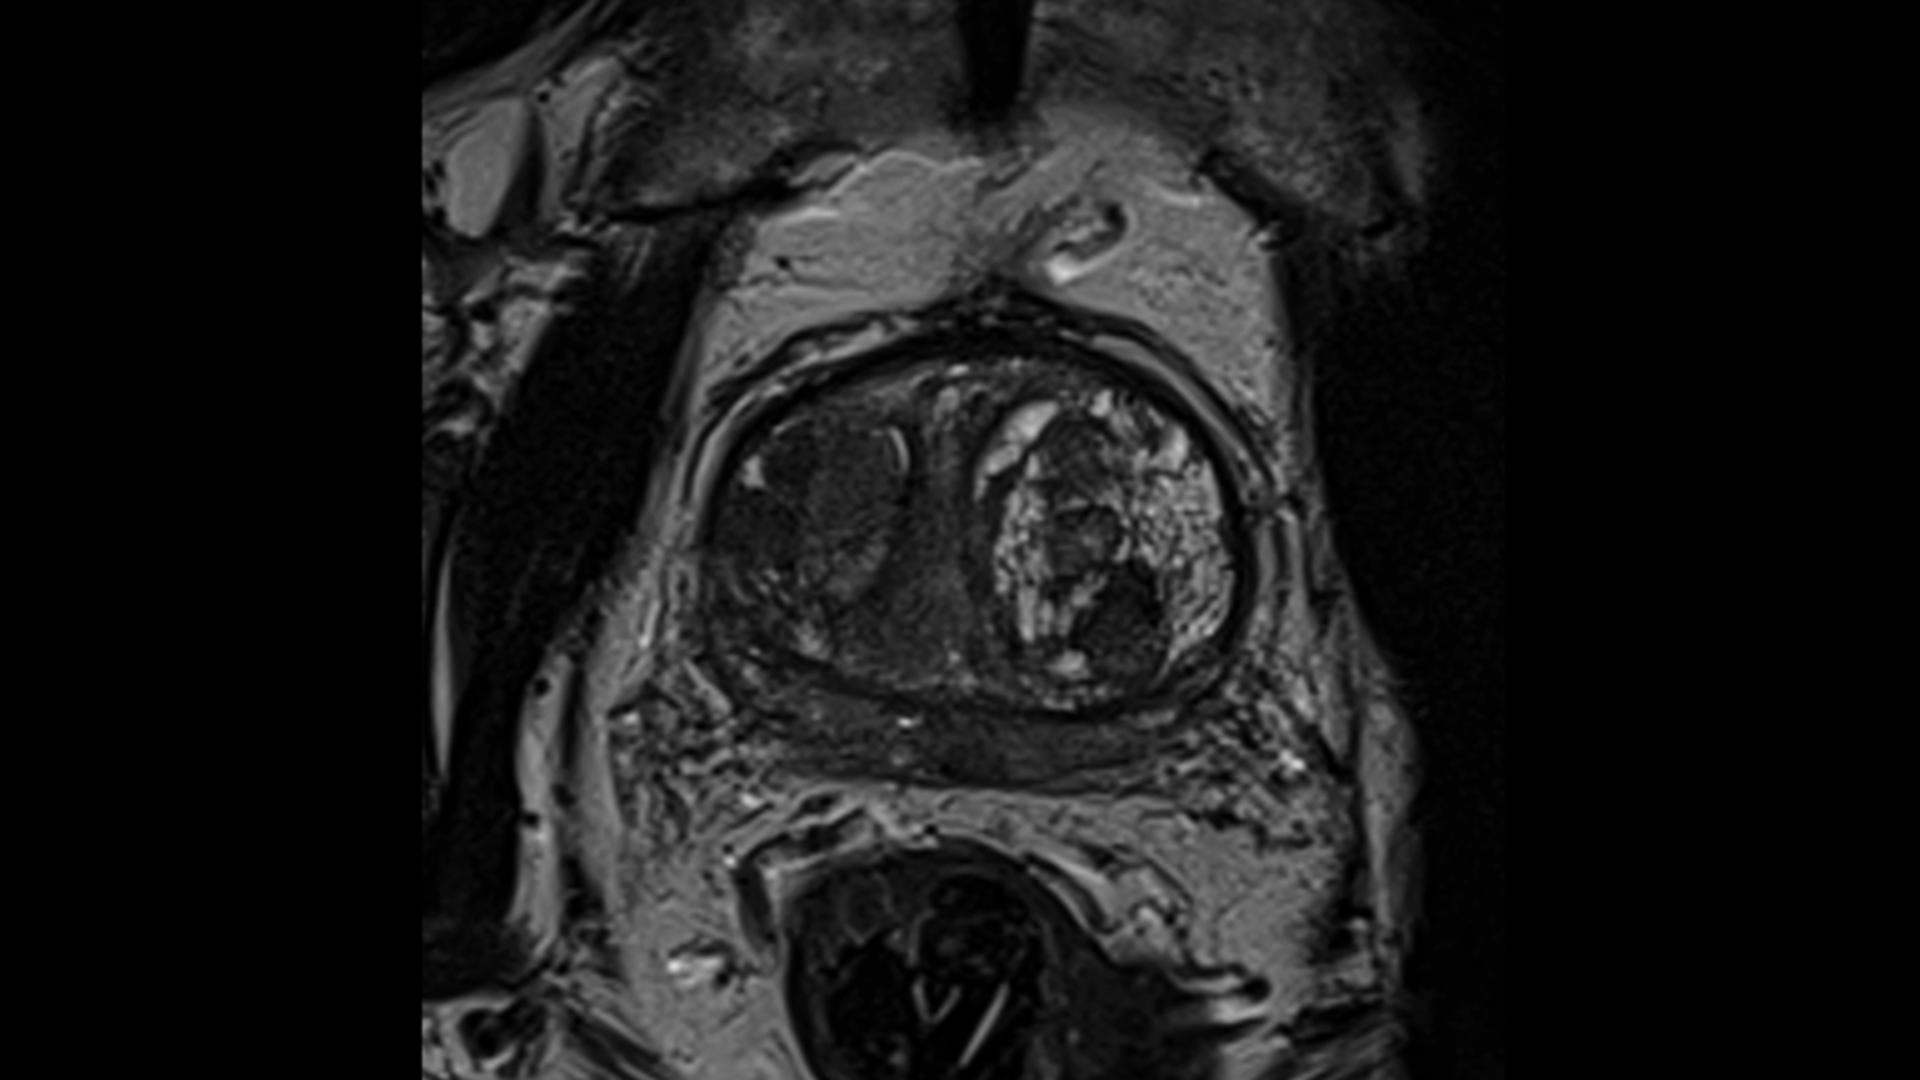

MAGNETOM® Skyra is the world's first 3 Tesla, 70 cm Open Bore Tim+Dot system By combining our pioneering deep learning image reconstruction technology Boost with our acclaimed acceleration techniques, MAGNETOM Skyra Fit achieves acceleration of up to 88%.

MAGNETOM Skyra's Onco Suite features a collection of sequences, protocols, and evaluation tools that guide users through the detailed assessment of a variety of oncological conditions. View and Download Siemens MAGNETOM Skyra owner's manual online Through the integration of groundbreaking Tim® 4G (Total imaging matrix) and DotTM (Day optimizing throughput), MAGNETOM Skyra sets a new standard of efficiency, ease of use, and care, which will help harness a new level of productivity

Buy Used Very Good SIEMENS Skyra 3T Online ⭐. Siemens Skyra 3T The Siemens MAGNETOM Skyra 3T is the world's first 70cm TIM 4G + DOT 3 Tesla strength MRI system with the smallest footprint of any 3T system currently on the market Through the integration of groundbreaking Tim® 4G (Total imaging matrix) and DotTM (Day optimizing throughput), MAGNETOM Skyra sets a new standard of efficiency, ease of use, and care, which will help harness a new level of productivity